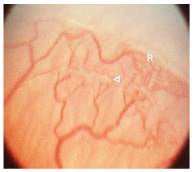

Página 323 - 9.3. Evolución de la ROP